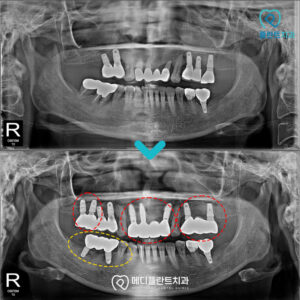

춘천수면치과 사랑니 발치는 믿을 수 있는 곳에서     안녕하세요:) 춘천수면치과 메디플란트치과입니다.   사랑니는 보통 10대 후반에서 20대 초반 사이에 나오기 시작합니다.   큰 문제 없이 지나가는 경우도 있지만 많은 경우 통증이나 잇몸 염증, 주변 치아 문제로 이어지기도 하는데요.   더보기…